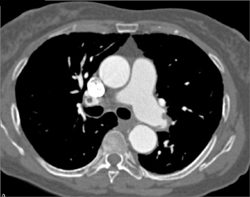

Pulmonary Embolism